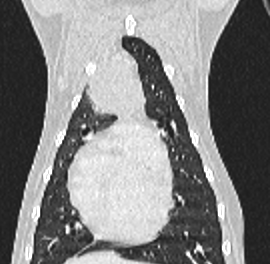

Hashtag, eine große Mischlingshündin, zeigt auf dem Röntgenbild ihres Haustierarztes eine große Masse im Thorax. Nach dem Staging mittels CT und Biopsie bei uns stand fest, eine Operation ist sinnvoll. Aus dem offenen Brustkorb wurde Hashtag ein mandarinengroßer Tumor entfernt. Die Narkose unter künstlicher Beatmung verlief problemlos. Nach Entfernung und dem Brustkorbverschluss unter Einlegen einer Thoraxdrainge, erholte sich Hashtag sehr schnell und wurde nach einigen Tagen entlassen.